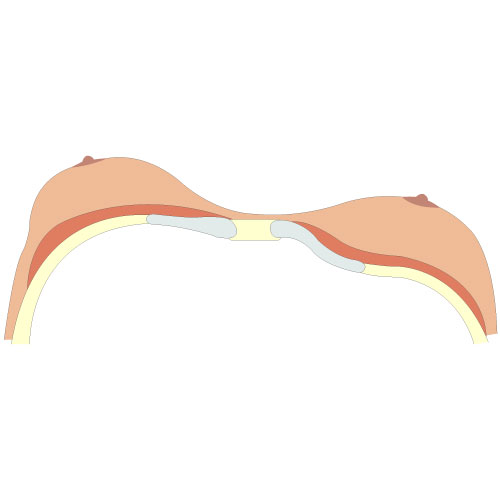

Disegno di Pectus Excavatum tipo 3

Viene stabilito tramite TAC nel punto più profondo della depressione: è il rapporto tra la larghezza e la profondità massima.

L'indice di Haller permette di misurare con maggiore precisione la profondità del petto escavato specialmente nelle donne, nelle quali la deformazione è difficile da valutare a causa del volume mammario. Quanto più l'indice di Haller è alto tanto più il Pectus Excavatum è profondo.